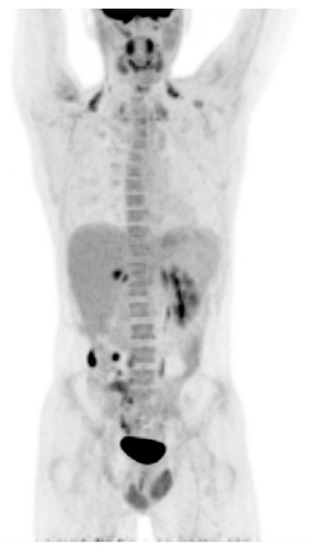

2. Case Report